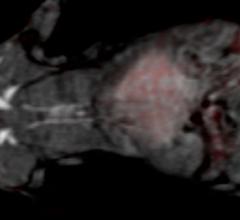

September 23, 2015 — New research describes a method, tested in rats, that may someday allow healthcare providers to ...